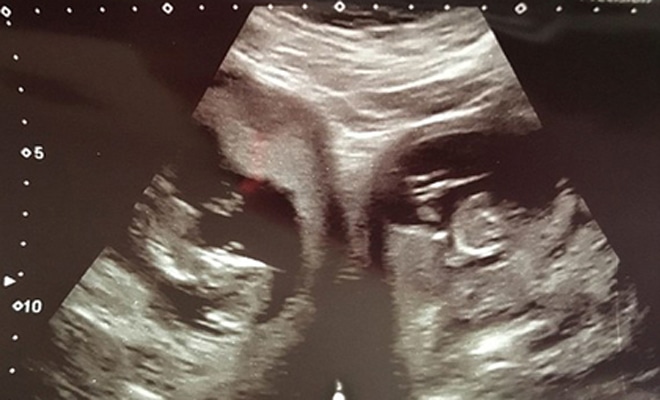

О необычном строении своего тела Эшвуд узнала только во время второй беременности. Во время первой врачи не заметили ничего особенного — Дженнифер родила здорового ребёнка. О патологии узнали лишь на 20-й неделе второй беременности, когда специалист увидел два плода в двух матках.

Эшвуд родила детей на 34-й неделе беременности посредством кесарева сечения. Младенцев назвали Поппи и Пиран.